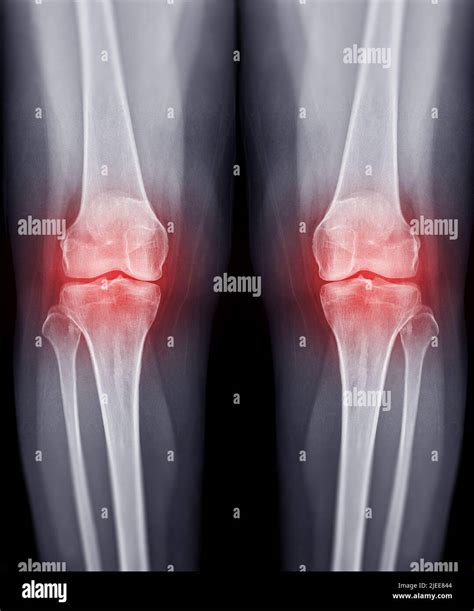

• Visible Swelling: The skin around the patella (kneecap) often looks puffy or taut compared to the unaffected leg.

• Imaging Studies: X-rays are often the first step to look for fractures or signs of arthritis. An MRI provides a detailed look at soft tissues like ligaments and menisci, which are invisible on standard X-rays.

• knee joint effusion X-ray